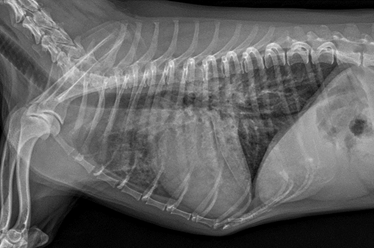

아래는 아이의 엑스레이 사진입니다.

검게 보여야 할 폐의 부분이 하얗게 보입니다, 더하여 방사선상 심장의 크기도 커 보입니다.

그렇습니다. 심장병에 의한 폐부종입니다.

퇴원 당시 방사선 사진 볼까요?

완벽하게 폐부종이 사라지지는 않았네요? 아이의 경우 병원에서는 워낙 밥을 잘 먹지 않고

예민했던 아이이기 때문에 무리한 입원보다는 응급 상황만 해소 후 퇴원 후 내원약으로 관리해보기로 하였기 때문입니다!